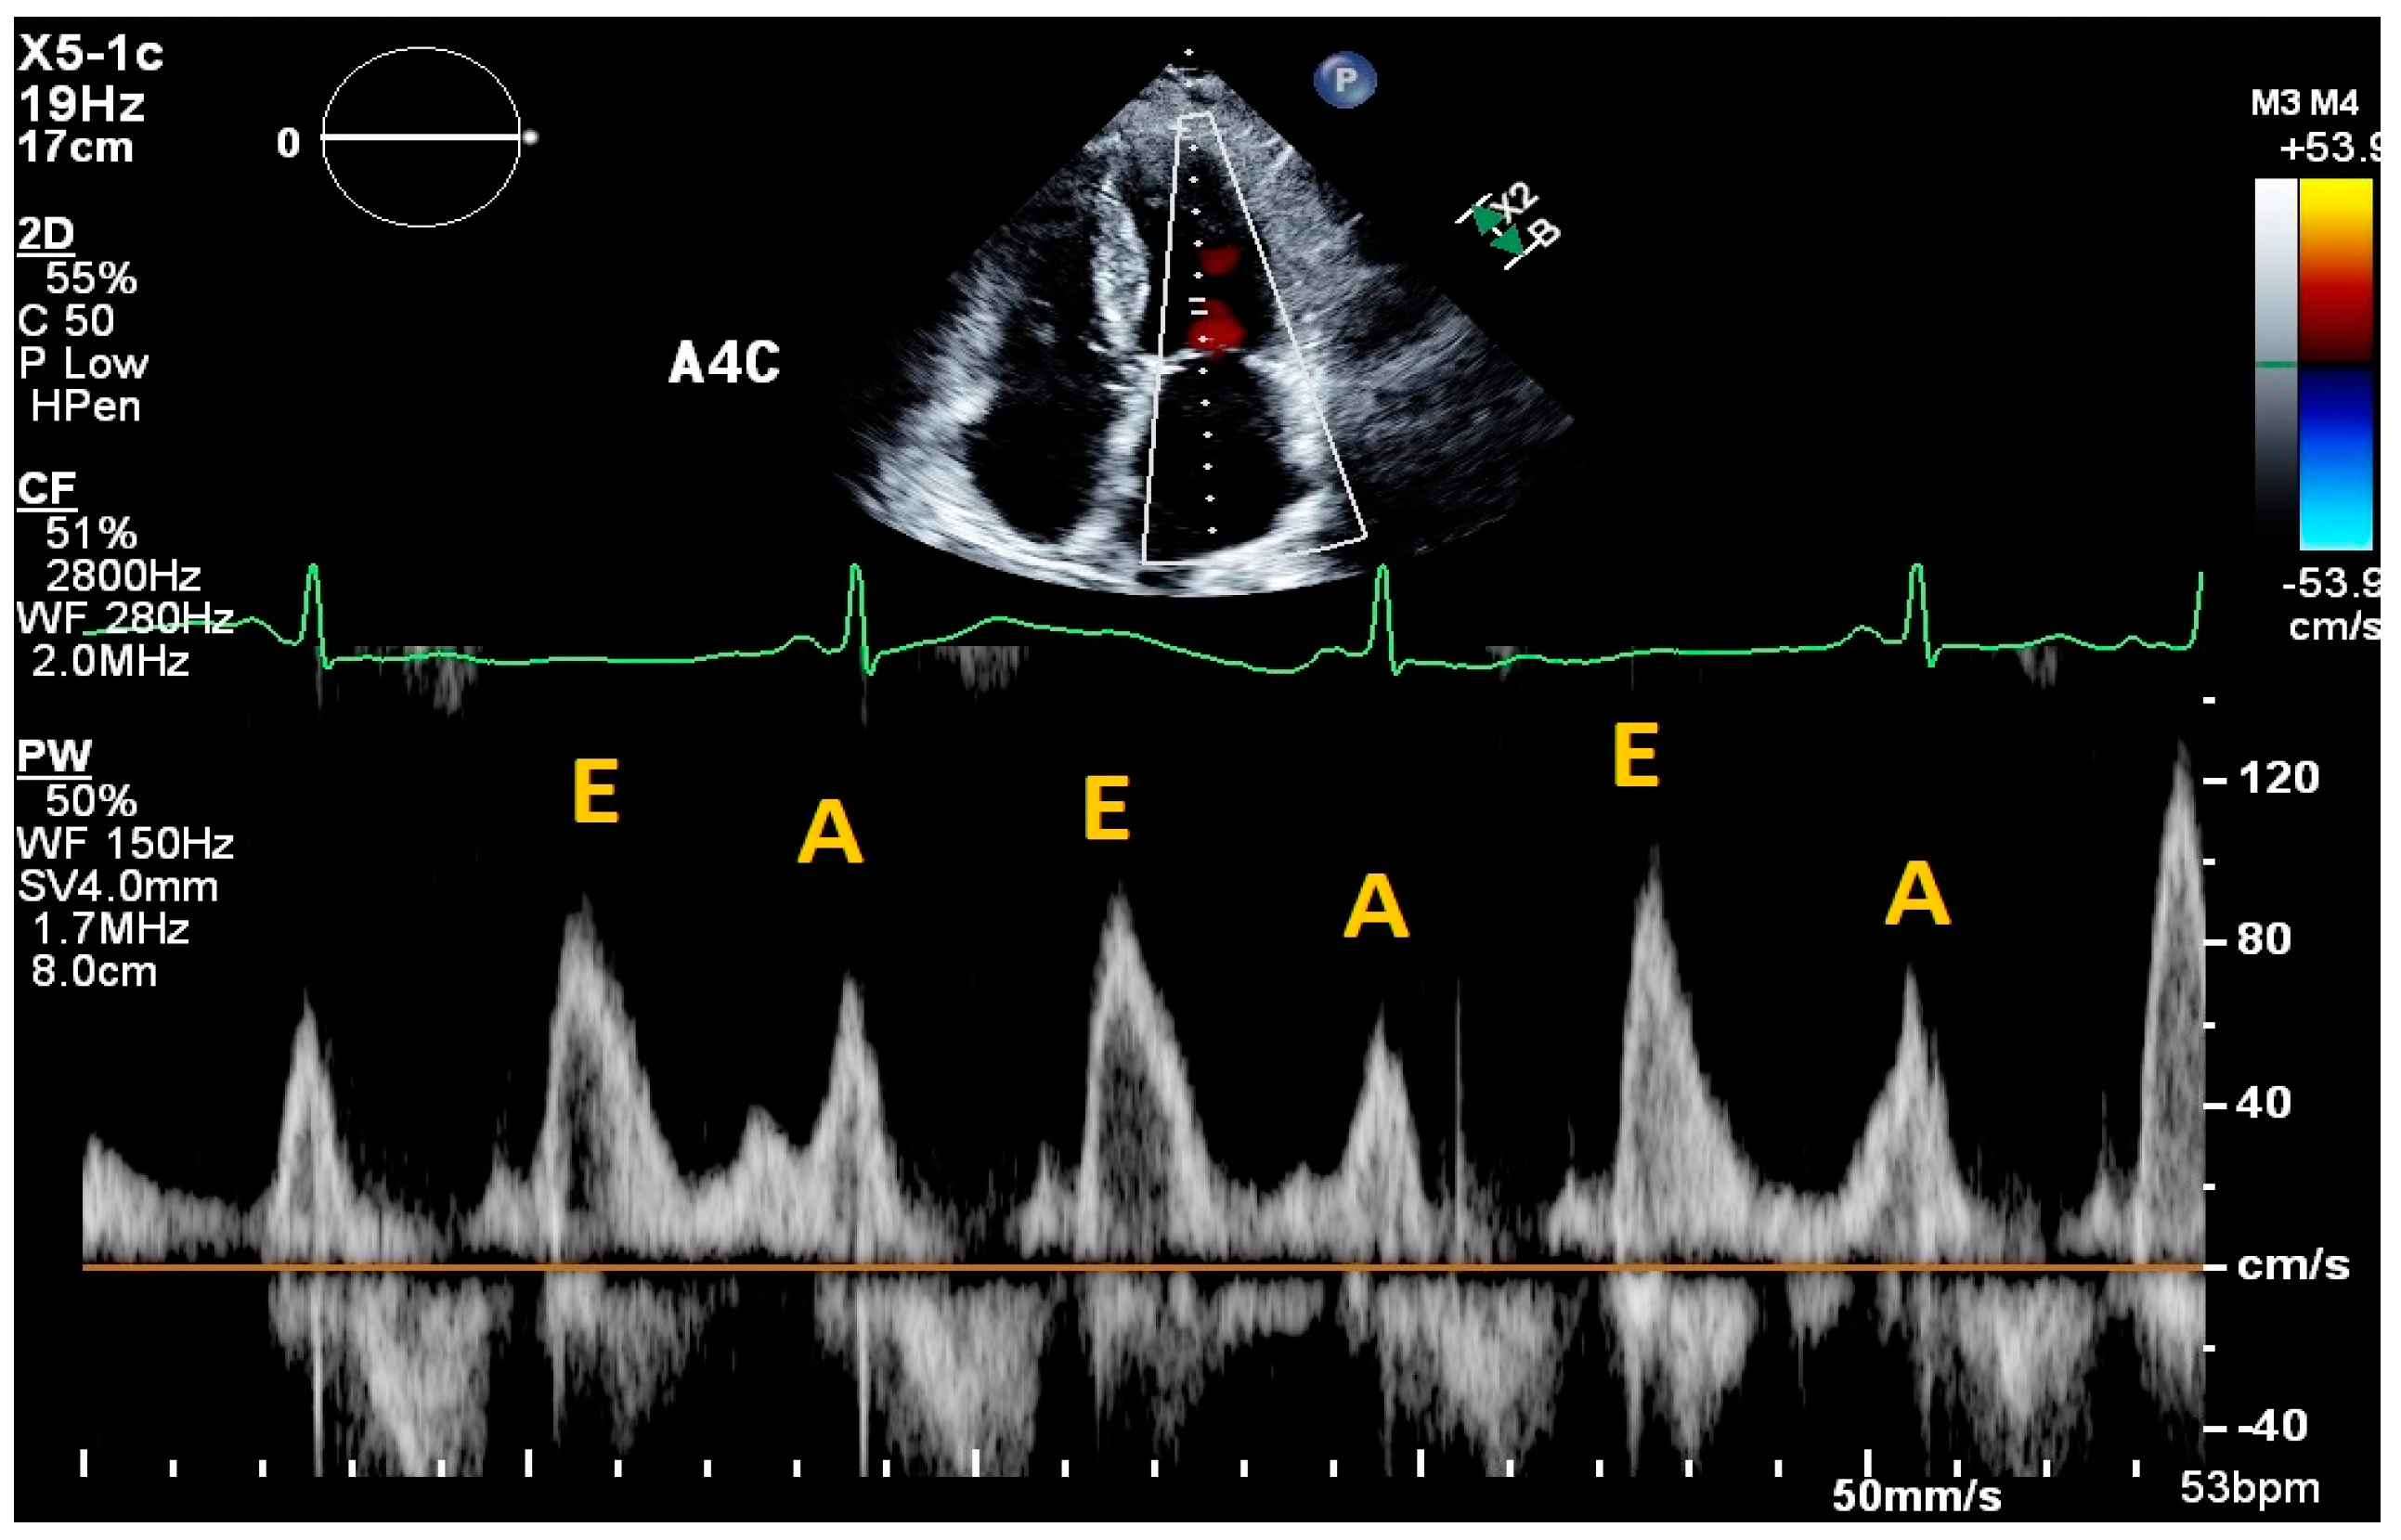

2. Cardiac Ultrasound

- Nagueh, S.F.; Smiseth, O.A.; Appleton, C.P.; Byrd, B.F., 3rd; Dokainish, H.; Edvardsen, T.; Flachskampf, F.A.; Gillebert, T.C.; Klein, A.L.; Lancellotti, P.; et al. Recommendations for the Evaluation of Left Ventricular Diastolic Function by Echocardiography: An Update from the American Society of Echocardiography and the European Association of Cardiovascular Imaging. J. Am. Soc. Echocardiogr. 2016, 29, 277–314. [Google Scholar] [CrossRef] [PubMed]

| Fletcher et al., 2020 [9] | Systematic review | Tricuspid inflow velocities | Patients with valvular disease, altered RV systolic function, recent cardiac surgery, acute heart failure, heart transplant, pulmonary hypertension, atrial fibrillation | Strength of correlation between E/e’ and RAP | 17 articles | Consistent positive correlation between E/e’ and RAP in patients with reduced RV systolic function; equivocal support correlating E/e’ and RAP in heart failure patients. |

| Mitral E/e’ ratio estimated from the E wave velocity of the mitral inflow Doppler envelope and the tissue Doppler e’ wave velocity at the mitral annulus (septal and/or lateral) | E/e’ ≤ 14 |

|

| |

| DT in the mitral inflow Doppler envelope | 160–200 ms |

|

| |

| Peak velocity of the TR jet | ≤2/8 m/s |

|

| |

| Estimated PASP using TR jet plus estimated RAP from IVC assessment | ≤35 mmHg |

|

| |